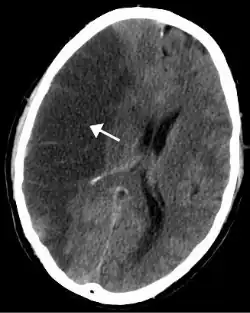

Risques de cancer

.jpg)

La consommation de tabac est la première cause de cancer connue dans le monde. Elle est impliquée dans 33,9 % des cancers mondiaux[40].